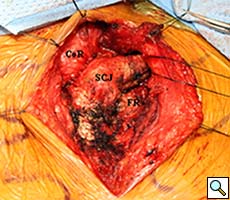

Intraoperatively, the gastric conduit was noted to be intimately compressed by the left SCJ (Figure 3A). The insertion of the sternocleidomastoid and other strap muscles were divided using electrocautery and the conduit was carefully bluntly dissected off the posterior sternum and left SCJ. The manubrial and clavicular segments of the SCJ were then resected, revealing the conduit underneath in good condition (Figure 3B). Care was taken to preserve the left internal mammary artery. Intraoperative EGD confirmed easy passage of the scope through the cervical anastomosis and into the gastric conduit with reduced extrinsic compression. Saline irrigation into the field and air insufflation of the conduit was used to confirm conduit integrity. A Savary-Gilliard guidewire was endoscopically passed and the anastomosis was carefully dilated using 42, 48, and 54 French (Fr) Savary-Gilliard bougie dilators (Cook Medical, Bloomington, IN) with minimal resistance. After removal of the guidewire, a 52 Fr Maloney dilator (Medovations, Milwaukee, WI) was also passed through the conduit without difficulty.